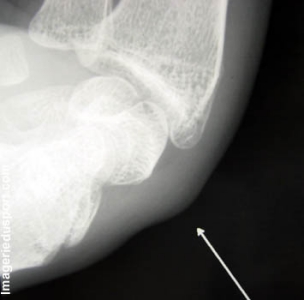

A - Radiographie de profil en flexion : Bombement des parties molles dorsale du carpe avec voussure sous cutanée.

Kyste synovial de la face dorsale du poignet.